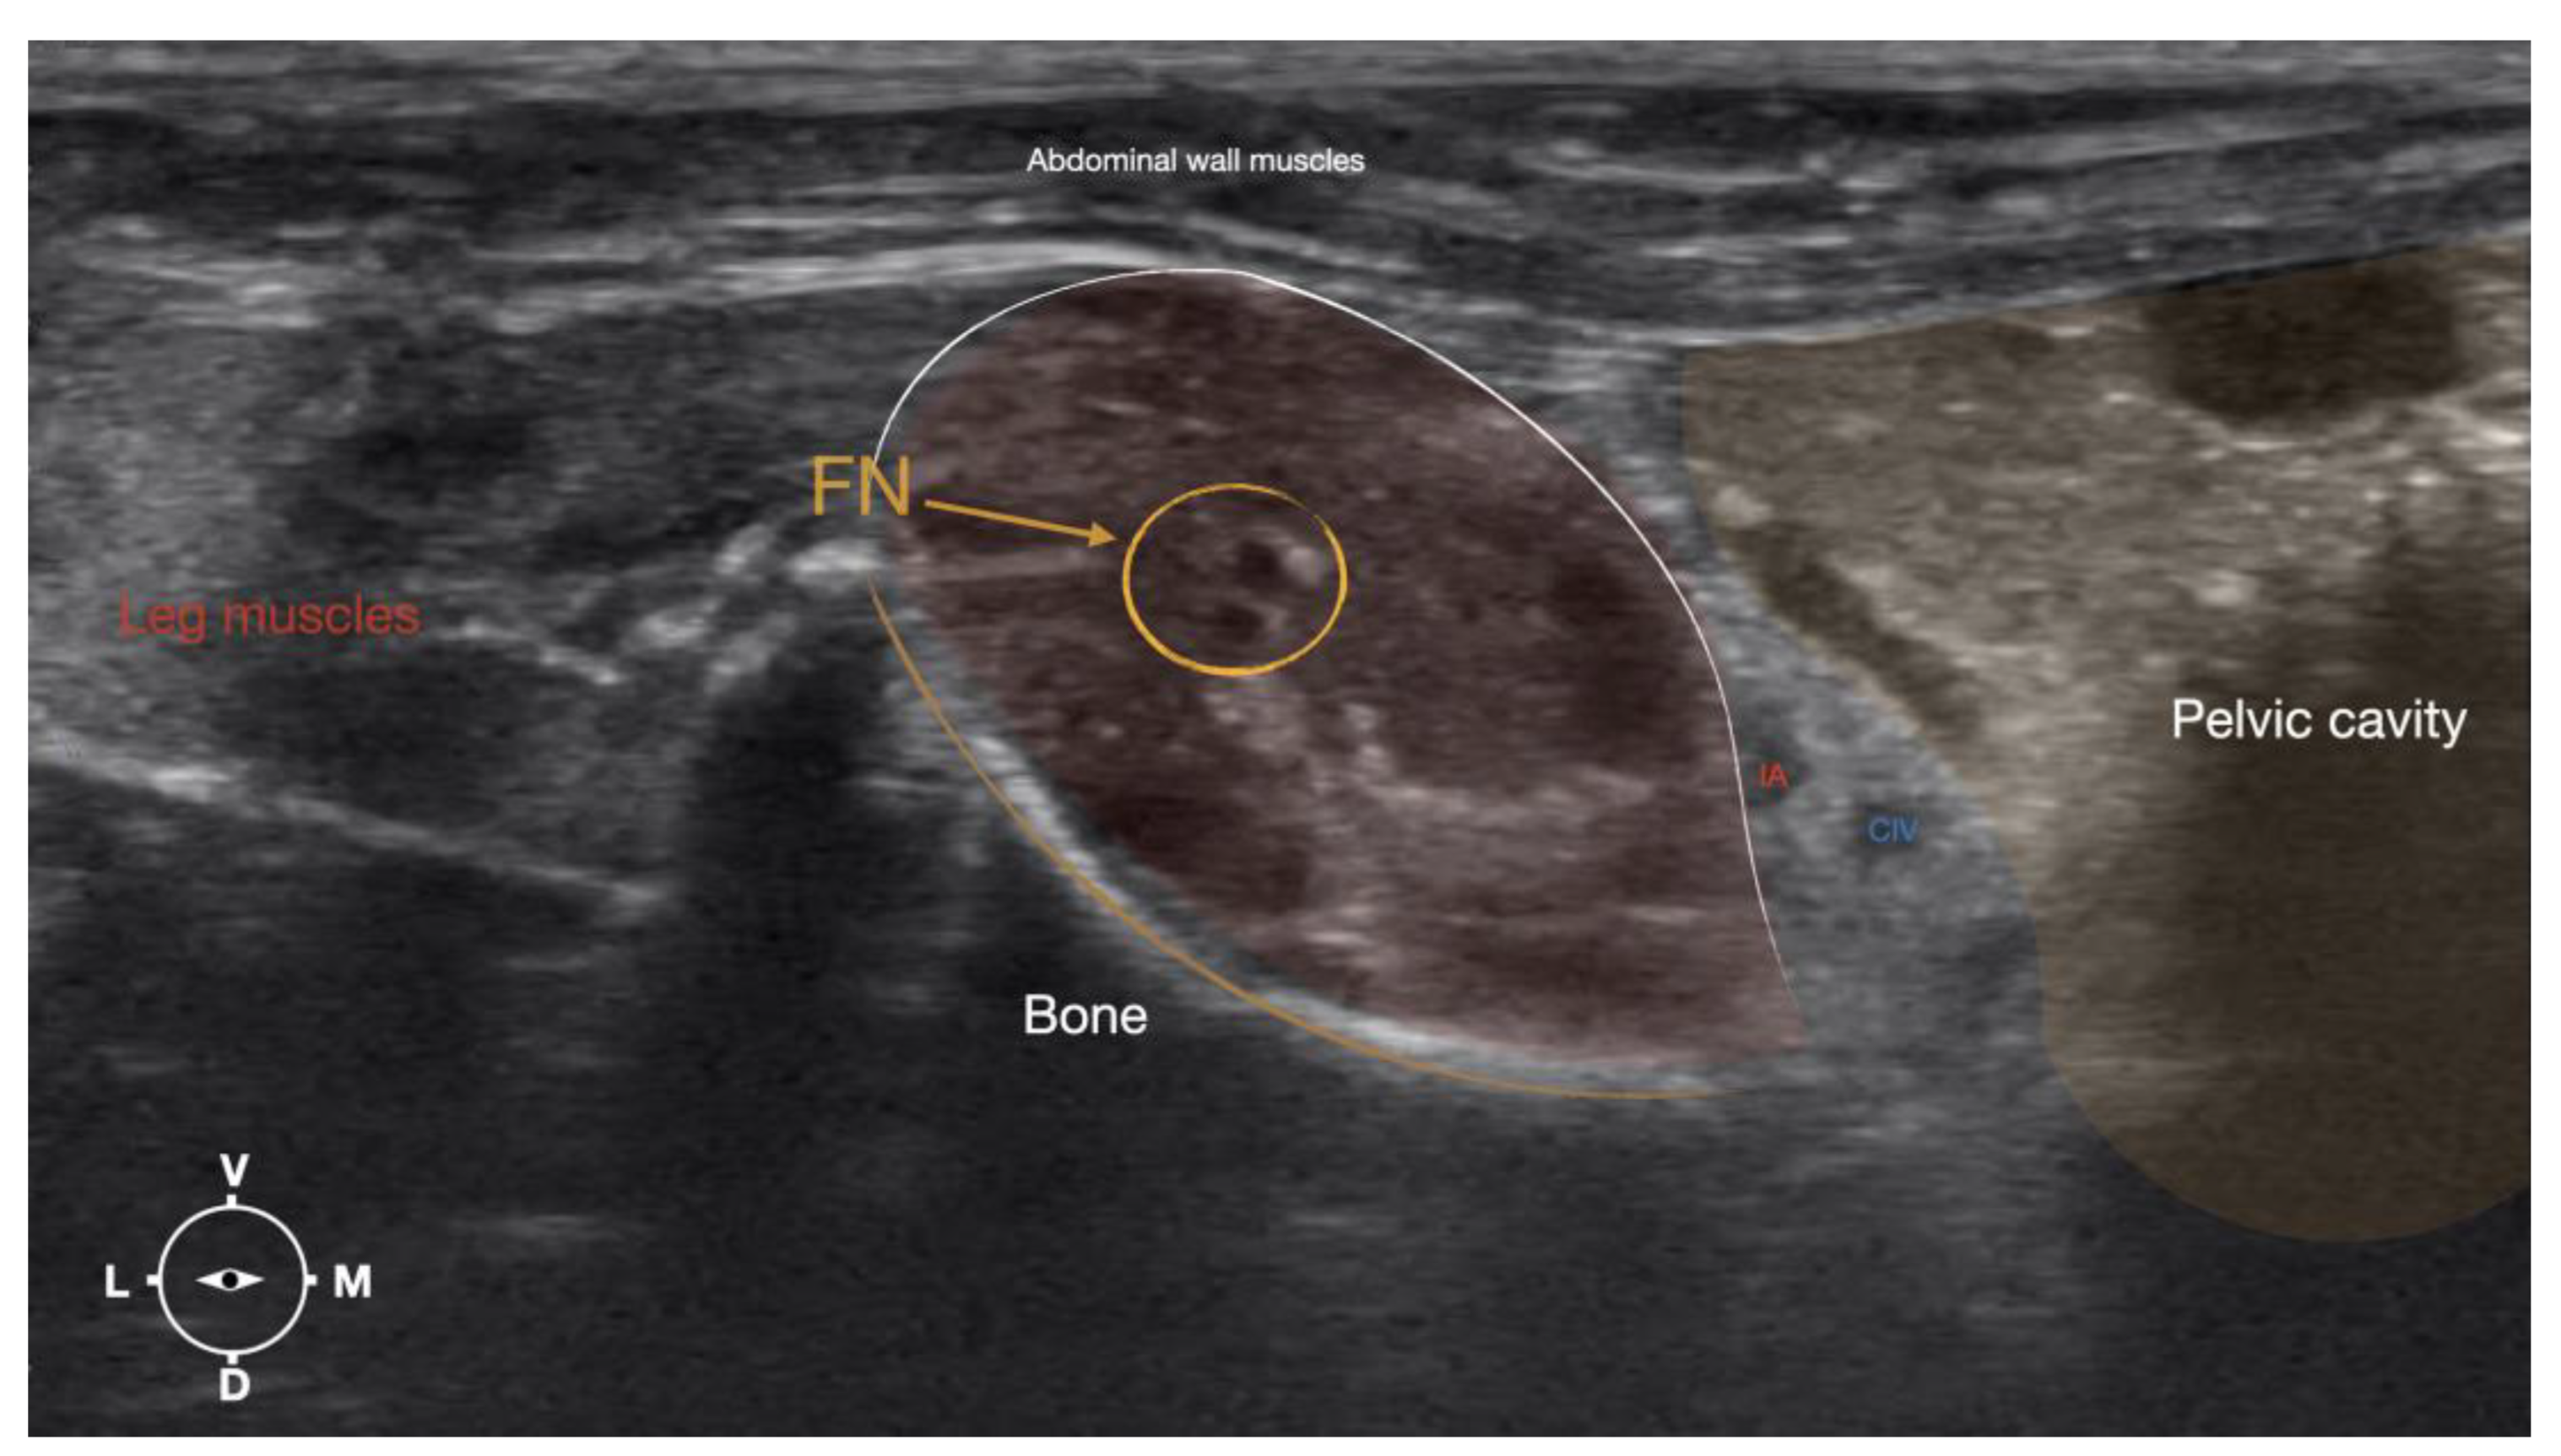

Figure 4. Corresponding transverse ultrasound image to the figure 5. The ultrasound image shows the FN and related structures. IA, iliac artery, CV, common iliac vein; FN, femoral nerve; Dm dorsal; L, lateral; M, medial; V, ventral.

Figure 6. Ultrasonographic image showing the approach of the needle towards the femoral nerve. IA, iliac artery, CIV, common iliac vein; FN, femoral nerve; D, dorsal; L, lateral; M, medial; V, ventral.

The cadaver was positioned in dorsal recumbency before the leg was extended caudally. The transducer was placed over the hypaxial muscles, transverse to the long-axis of the spine, and at the level of the projection of the iliac crest. Then, the transducer was moved in caudal direction along the IPM until the femoral nerve was clearly seen in the substance of the IP (Figure 4). A 50mm 22 gauge insulated needle (Sonoplex Stim Cannula, Pajunk Medical Produkte GmbH, Germany) prefilled with a 1:1 solution of new methylene blue (MethyleneBlue1%w/vaq.soln, AlfaAesar, Thermo FischerGmbH, Germany) and lidocaine (Xylanest purum 2%, Gebro Pharm GmbH, Austria) (L-NMB) was inserted using an in-plane approach. The needle was inserted at the lateral edge of the transducer, and advanced in-plane under sonographic guidance through the iliac fascia and IPM in a dorso-medial direction towards the femoral nerve (Figure 5 and Figure 6). The needle was advanced until its tip was located in vicinity to the femoral nerve. A test volume of 0.05 ml of L-NMB was injected to confirm adequate distribution. The remaining volume of 0.15ml/kg was then injected extraepineurally around the femoral nerve.

The femoral nerve was found in the substance of the IPM with a dorso-ventral trace (Figure 8). It was divided into branches before it left the substance of the IPM to enter the leg through the vascular and muscular lacuna.

Based on the anatomical dissection and the US scans performed in this phase, the best way to locate and inject the FN was achieved by scanning the IPM from the projection of the iliac crest in caudal direction. Ultrasonographically, the femoral nerve appeared as a hypoechoic structure in the dorsal part of the IPM, becoming hyperechoic/honey-comb-like in the ventral part of the mentioned muscle. The IPM was displayed as structures with heterogeneous echogenicity. The ilium and the vertebrae were displayed as a hyperechoic structure with acoustic shadow and located lateral and dorsal to the femoral nerve, respectively.